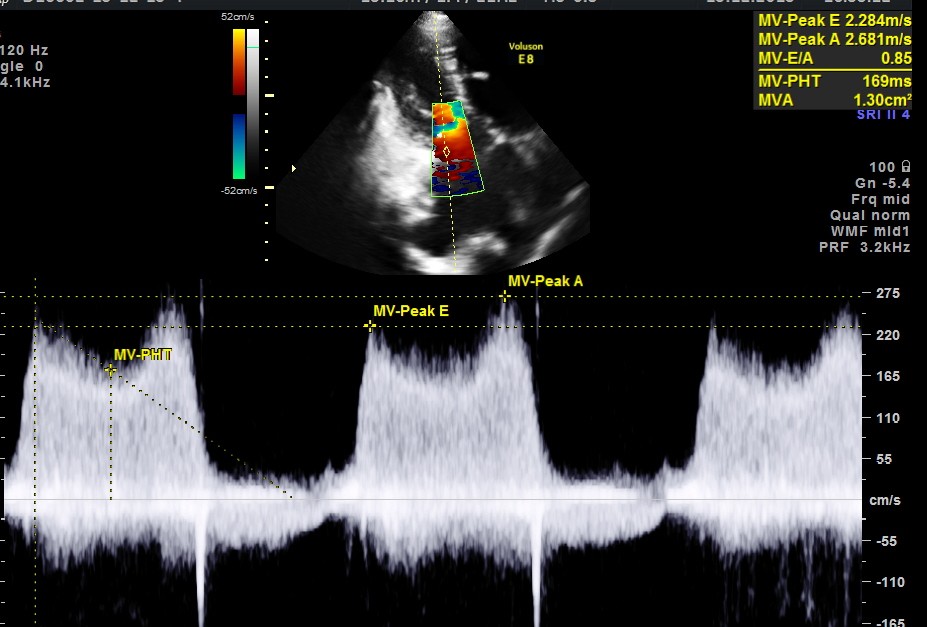

Her Echo cardiogram showed the following findings :

another normal mitral flow clipping is given below for comparison :

This patient had Rheumatic heart disease , moderate mitral stenosis with pulmonary hypertension .